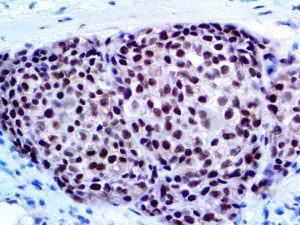

It is the ICU physician who is most likely to witness one of the deadliest manifestations of the abnormal immunological response, the cytokine storm syndrome (CSS). This response is also referred to by some as the cytokine release syndrome (CRS). CSS is characterized by continuous activation and expansion of macrophage and lymphocyte populations, which secrete large amounts of cytokines, causing the cytokine storm. This massive cytokine release is akin to hemophagocytic lymphohistiocytosis (HLH) disease, a syndrome characterized by initial unchecked and persistent activation of cytotoxic T lymphocytes and NK cells.

Clinical and laboratory manifestations of HLH include fever, enlarged liver and/or spleen, neurologic dysfunction, coagulopathy, liver dysfunction, cytopenias (i.e., low levels of erythrocytes, leukocytes, and/or platelets), hypertriglyceridemia, hyperferritinemia, hemophagocytosis, and eventually diminished NK cell activity as the immune system becomes progressively paralyzed. HLH can be familial (primary HLH) or secondary to another disease process (sHLH), such as rheumatic disease, in which it is referred to as macrophage activation syndrome (MAS, characterized by elevated ferritin).